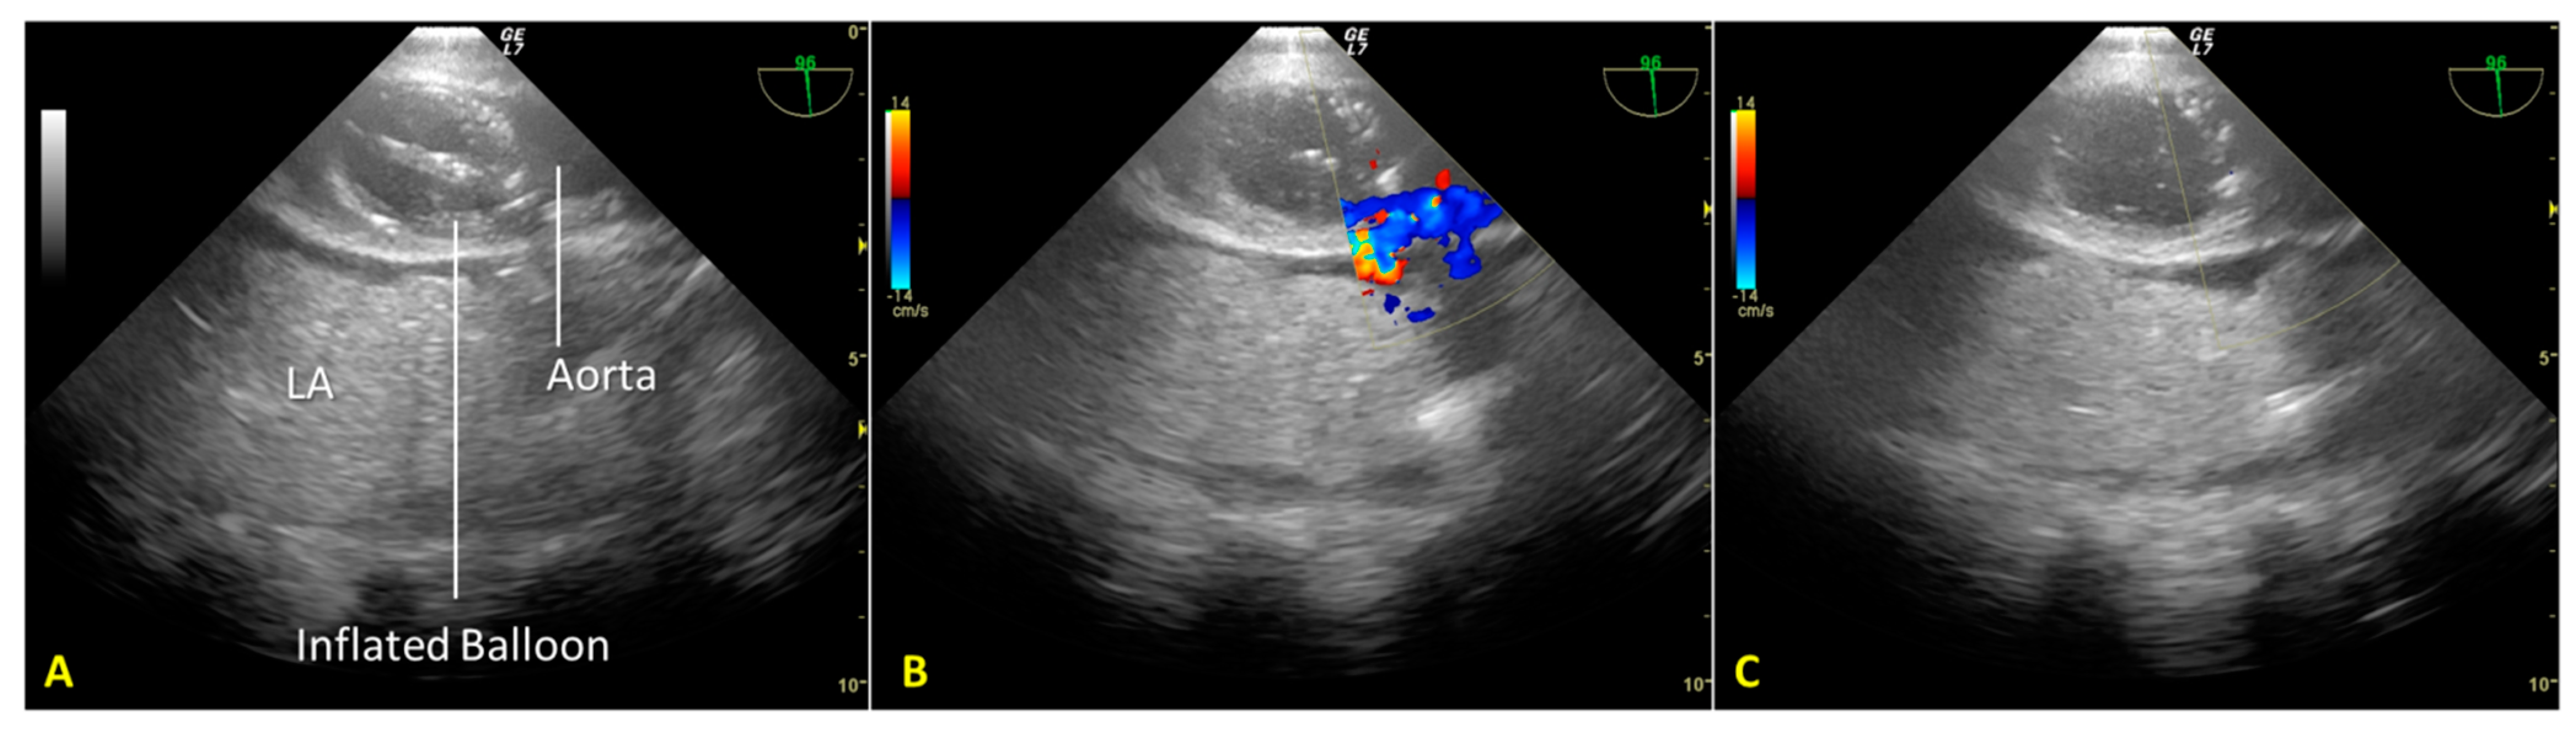

Cardiac arrest occurred rapidly with the cessation of life support. After checking the asystole on continuous ECG monitoring for twenty minutes (“no-touch period”), we certified the patient’s death. We performed post-mortem percutaneous femoral cannulation using the previously placed introducer wires. A 19 Fr cannula was placed in the right femoral vein (draining cannula) and a 17 Fr cannula in the right femoral artery (reinfusion cannula). Before starting the A-NRP, we inflated the AB according to the manufacturer’s instructions, which—considering the thoracic aorta diameter of 30 mm, as measured from a recent CT exam—was with 19 mL of saline (Figure 2A). We set extracorporeal blood flow to be greater than 2.4 L/min/m2, corresponding to half of the patient’s body surface area.

Nevertheless, abdominal aortic regional pressure remained consistently suboptimal (approximately 45 mmHg) [12]. A transesophageal color Doppler echocardiography scan to obtain a mid-esophageal descending aortic long-axis view demonstrated incomplete occlusion of the thoracic aorta (Figure 2B). Due to atheromatous plaques, the incomplete aortic occlusion required an additional 15 mL of saline. Real-time US-guided insufflation made filling the aortic balloon (AB) possible. AB is just enough to achieve total aortic occlusion but not so much as to risk balloon hyperinflation, which could cause aortic rupture, balloon rupture, and abdominal AB extension with celiac trunk occlusion (Figure 2C).

Figure 2. (A). Mid-esophageal descending aortic long-axis view scan: the endovascular occluder (RELIANT® catheter balloon, Tamworth, UK) is visible in the descending thoracic aorta. (B). Incomplete occlusion of the thoracic aorta during the initial phase of regional extracorporeal support for organ retrieval. Transesophageal color Doppler echocardiography documents the passage of blood around the aortic occluder. (C). Complete occlusion of the thoracic aorta after additional filling of the RELIANT® AB. Absence of blood flow in the thoracic aorta above the occluder. LA—lung atelectasis.